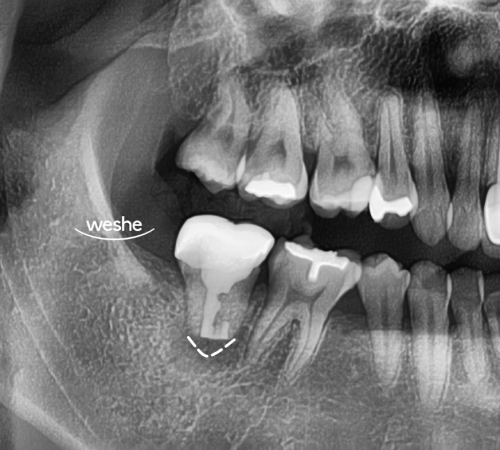

마곡 치과에서

치아 재식술을 진행할 때는

뿌리 훼손 없이 빠르게

발치를 시행해야 된다 설명해 드립니다.

이를 빼낸 뒤 치근단 부위를 확인하면

다량의 염증 조직이 관찰될 때에는

20250716

염증을 깨끗하게 제거하고,

근관 내 세균 침투를 방지하기 위해

MTA 등 생체친화적 재료로

역충전하여 밀봉합니다.

그 후 이를 원래 위치에

재식립하고 고정하는데,

이 과정에서 구강 외 시간이

30분 내외로 제한되어야

치주 인대 세포가 생존하고

뿌리 흡수를 방지할 수 있습니다.